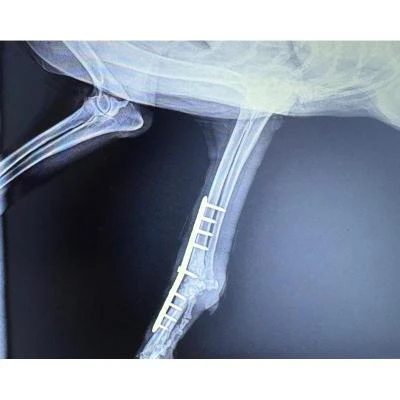

A cirurgia veterinária inclui procedimentos cirúrgicos de diferentes especialidades, como ortopedia, odontologia e emergências, planejados com base em exames detalhados e avaliação clínica.

Esse cuidado integral promove a recuperação funcional, alívio da dor e qualidade de vida dos animais, assegurando a segurança e a confiança dos tutores.

Importância do acompanhamento pós-operatório

Após a realização de um raio x e procedimentos cirúrgicos, o acompanhamento pós-operatório é essencial para assegurar a segurança do animal, prevenir complicações e promover uma reabilitação eficaz.

Com cuidados adequados e orientações dos profissionais de saúde veterinária, é possível assegurar a recuperação completa do pet e sua qualidade de vida a longo prazo.